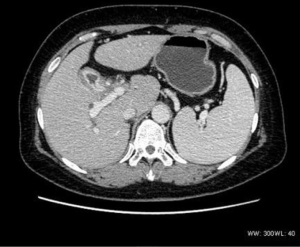

There were five cases of breast carcinoma (two of the left breast, and three of the right). Three cases were single onset, while two had multiple origins located in the upper quadrant of the right breast and behind the nipple. Macular calcification was visible in two cases. In addition, three cases were lobular in shape and had an obvious enhancement, while two cases had a blurred border, which mainly manifested as marginal enhancement and central necrosis (Figure 1). In addition, one case had skin invasion, two cases had clavicular region and axillary lymph node metastasis, and one case had lumbar, liver, and right lung metastasis.

The density was uneven in the five mediastinum tumor cases, which included one case with patchy vcalcification. Four cases had uneven enhancement after the dynamic enhanced scan, and one case exhibited obvious enhancement. All five cases had lymph node metastasis. Furthermore, one case had multiple metastases of the bilateral lungs, subpleural, liver, and bone (Figure 3), and one case had involvement of the left and right pulmonary arteries and superior vena cava. In two cases the metastasis involved the pericardium and mediastinum pleura.